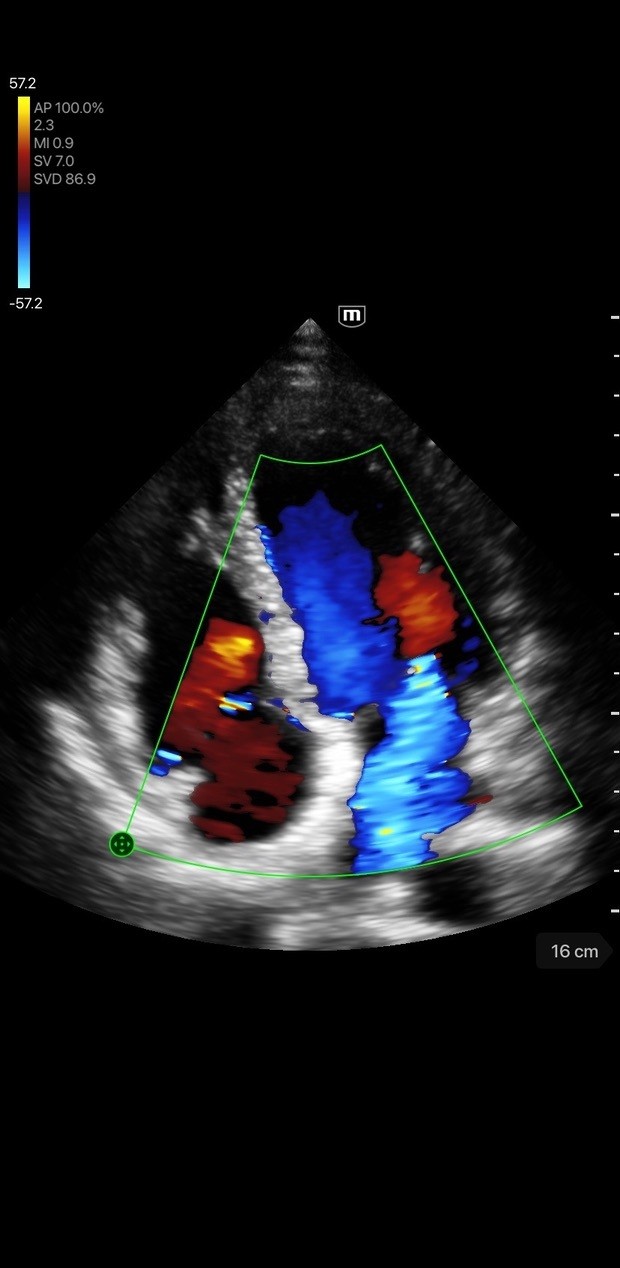

Loved Across Specialties

From Women’s Health to Cardiology and beyond, discover how Trice empowers providers with specialty-specific solutions.

Cardiology

Cardiology